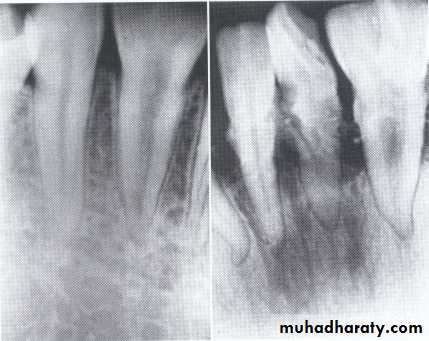

Dentin dysplasia, type II. panoramic &periapical films of the same case show obliteration of the pulp chamber, reduction in the caliber of root canals, and pulp stones obscuring the flame-shaped pulp chambers.

Periapical inflammatory lesions are associated with some of the mandibular anterior teeth.